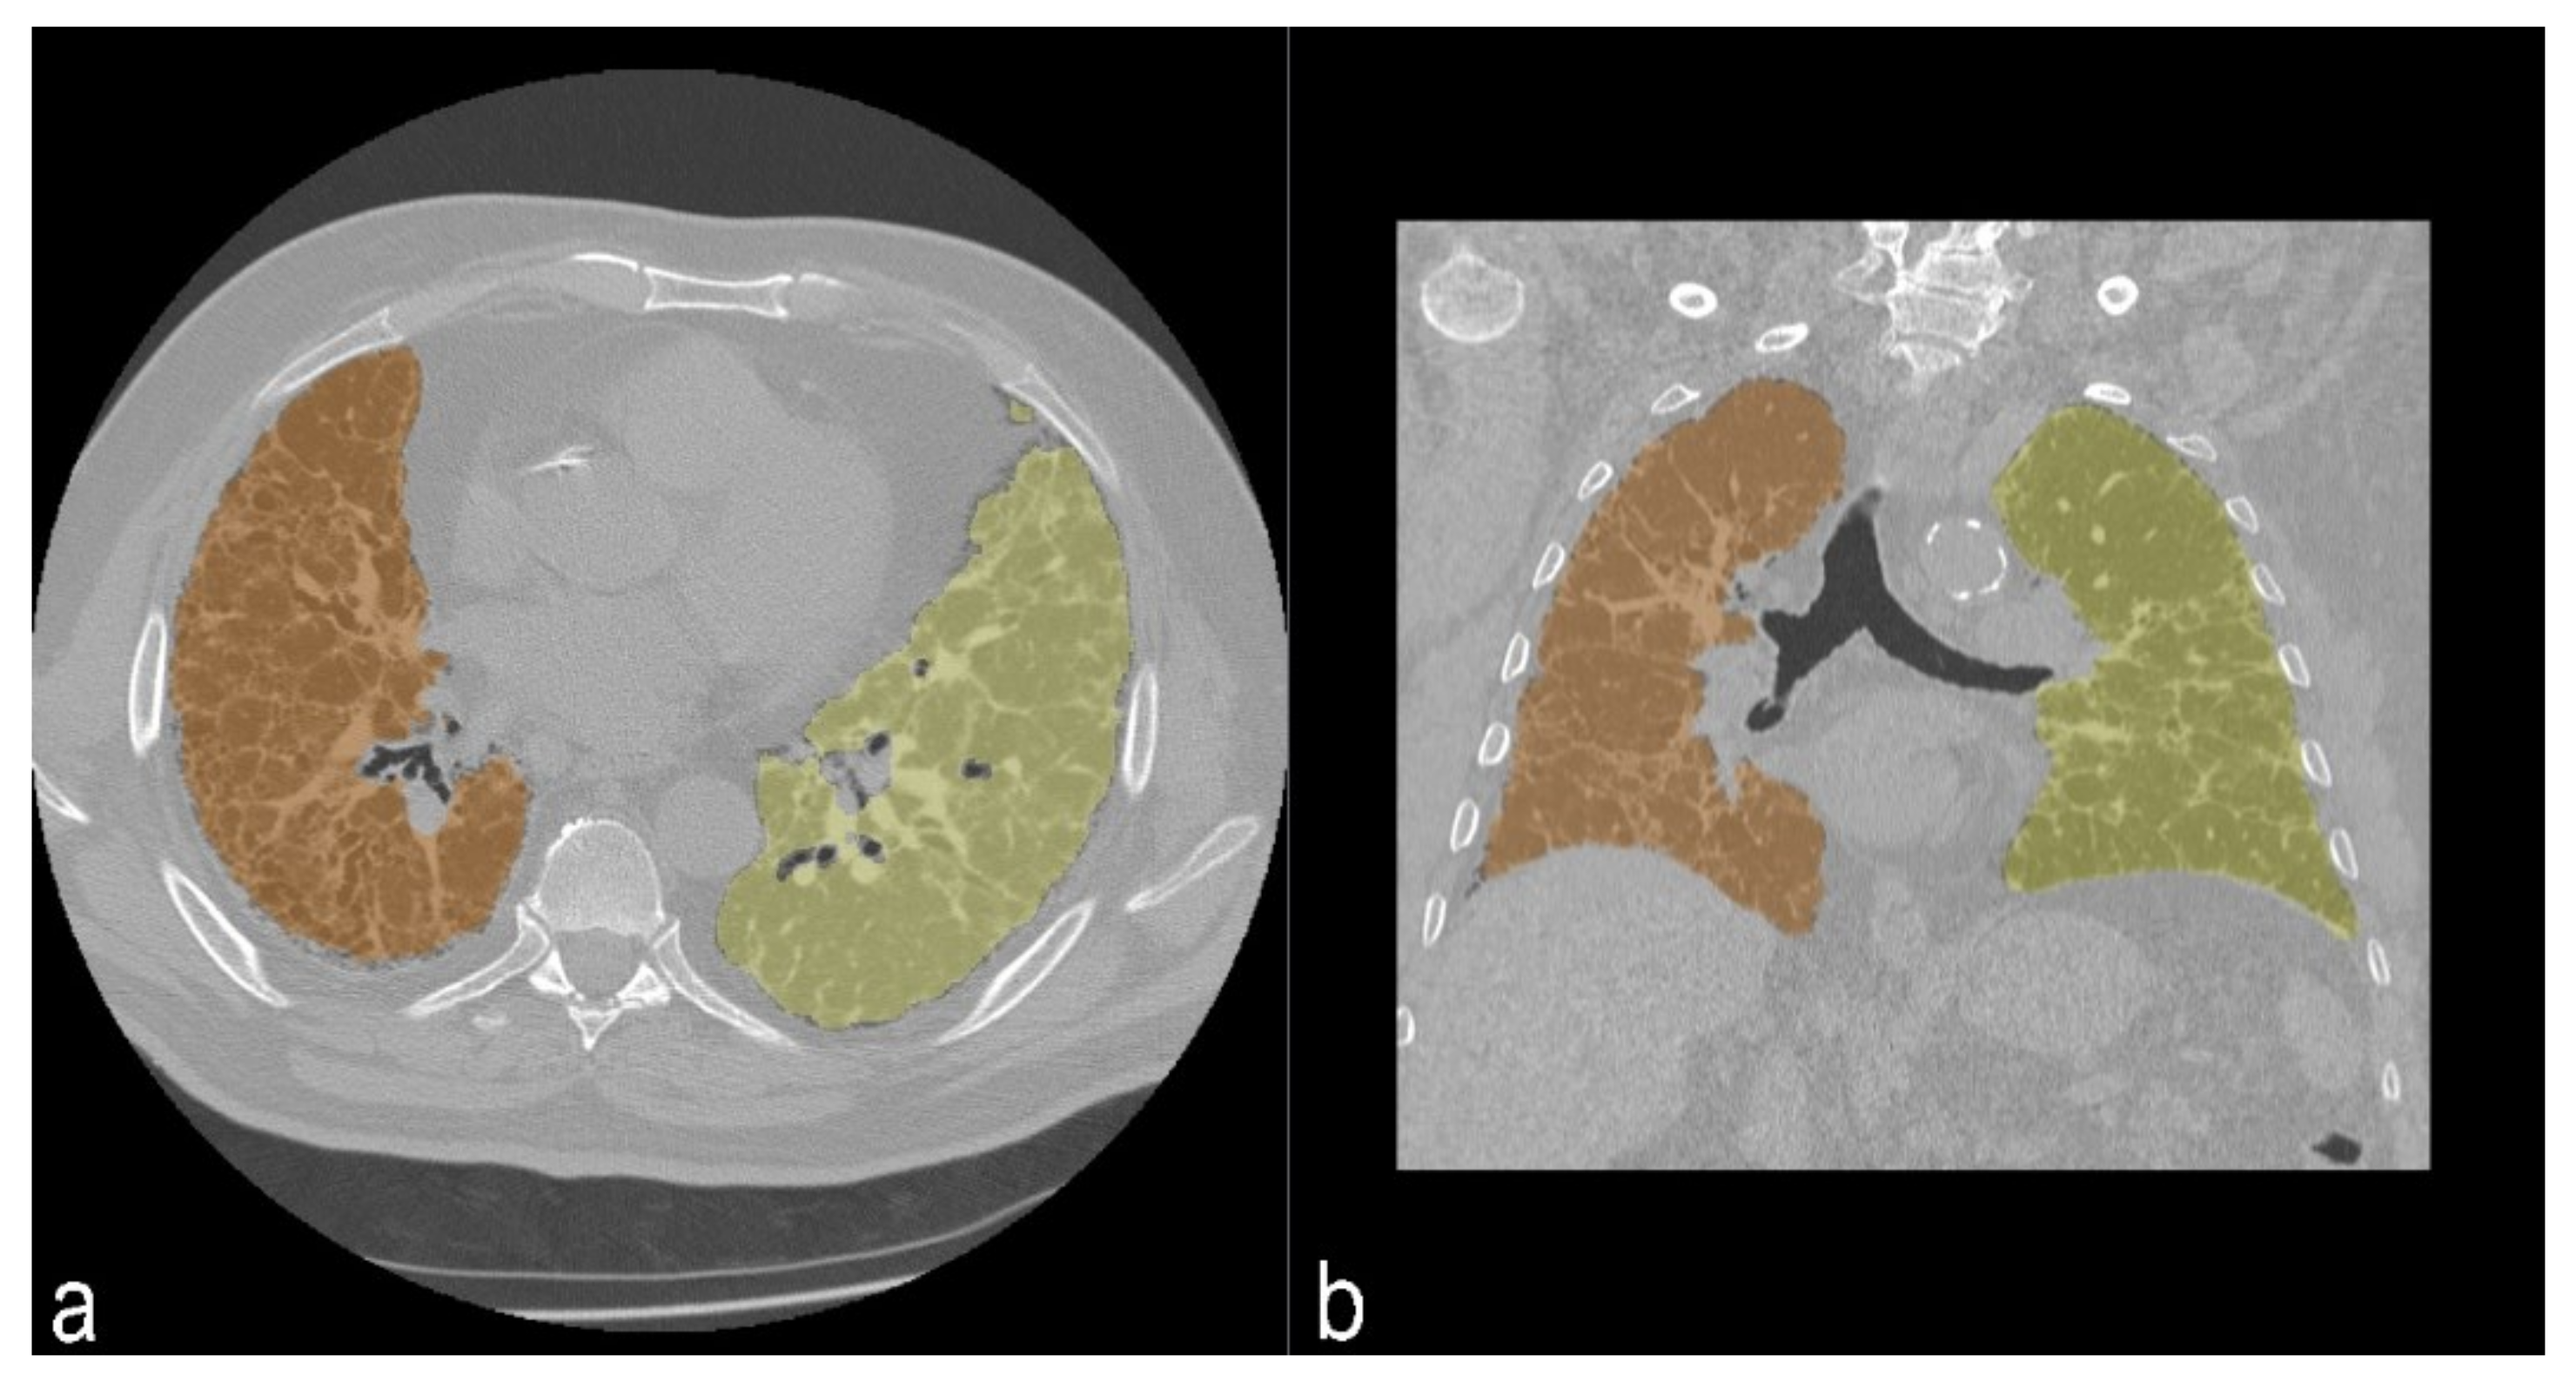

The quantitative analysis was performed using 3D Slicer © (SlicerCIP4-8-1), an open source software platform for medical image informatics, image processing, and three-dimensional visualization. The lung volume was automatically segmented from the surrounding tissue and divided into three zones of the same size. This tool used an algorithm to isolate the lungs from other tissues and structures selecting pixels between −200 HU and −1.024 HU (Figure 5). Axial segmented images were then visually inspected by the readers and excluded if segmentation was inaccurate. Then, the HRCT attenuation histogram of the lungs was derived and specific parameters were automatically calculated. Quantitative CT indexes have been proposed as useful and standardized methods for analyzing and rating the extent of ILDs.

Figure 5. Segmentation of lung parenchima in axial view (a) and coronal view (b). In orange, segmentation of right lung; in yellow, segmentation of left lung.